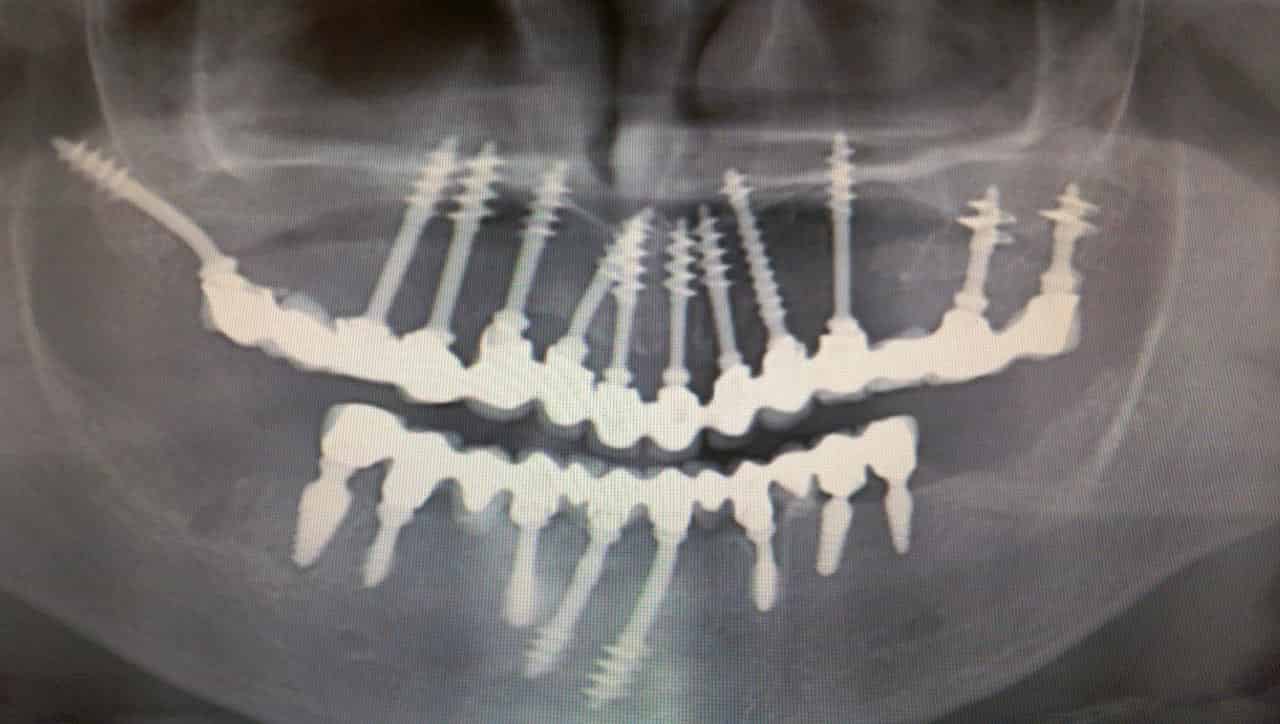

A modern kor nagyszerű technológiája számos vívmánnyal örvendezteti meg az emberiséget, aminek egyike a fájdalommentes fog implantátum beültetés. Az úgynevezett BEMER mágnesterápia a gyógyulási folyamatokkal járó kínzó tüneteket is hatékonyan csillapítja, sőt, gyorsítja is. Ne húzzuk-halasszuk az időpontfoglalást, hiszen amint azt a fenti példa is remekül mutatja, nincs mitől félnünk!